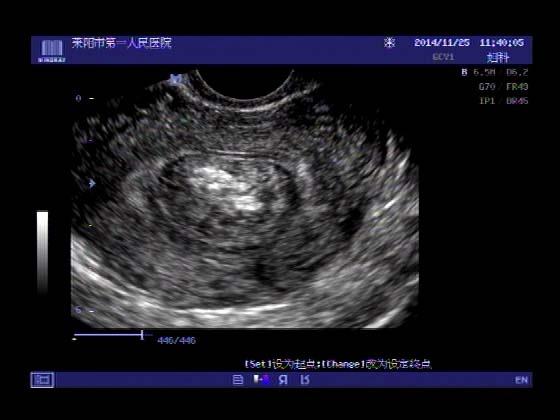

超声入门贴379---------粘膜下肌瘤(阴超的魅力)

女,43岁,月经量多3个多月,加重一个月

外院彩超检查提示:子宫后肌壁略高回声团------肌瘤?息肉?,盆腔少量积液

今天来我院检查:

巧妇难为无米之炊,经腹部超声确实很难定,阴超一目了然,乡镇医院诊断水平的提高更迫切的需要高档仪器的引进!